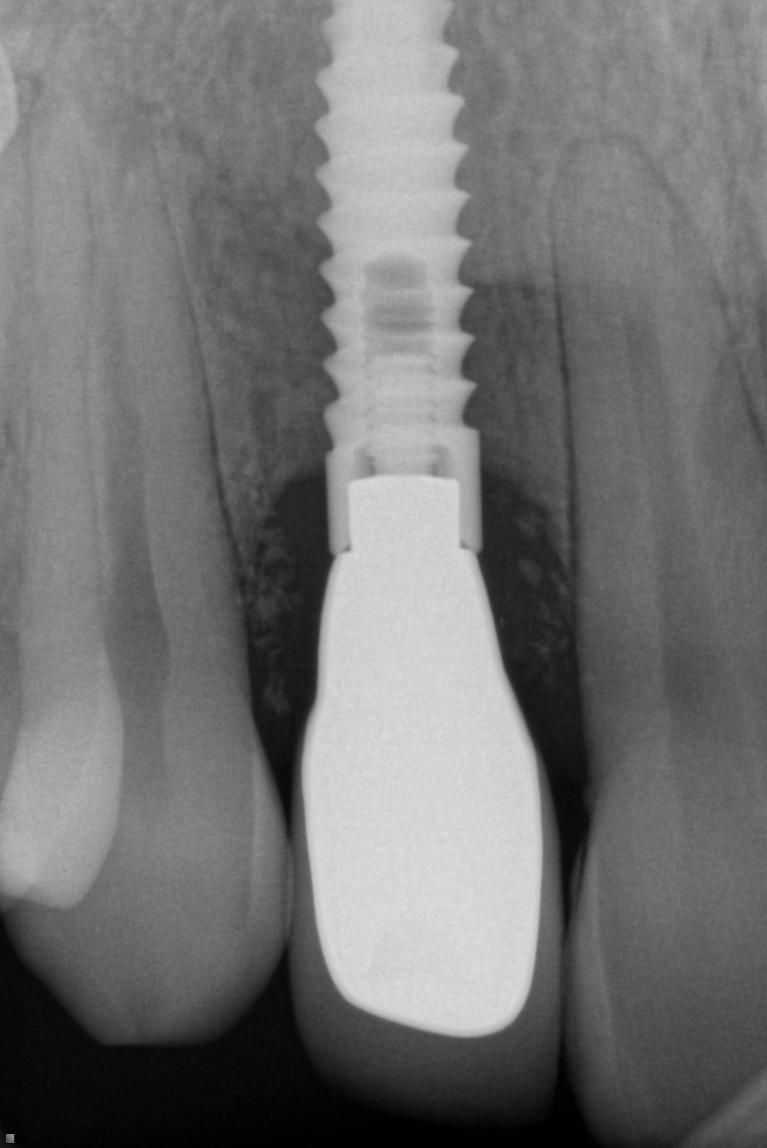

There are various reasons we do crowns as well as various processes involved.  Most of the time, after a tooth is prepared and an impression taken, we can have the crown ready to cement in two weeks.  Crowns on implants will often require an additional week to make as implant components must be ordered by the lab and custom parts fabricated.  Those additional steps require more time at the lab.

We choose the material we use based on needs.  Location plays a big role as back teeth do more work and would benefit from more strength, while front teeth don’t do as much of a chewing load, but are required to look good.  As fear as strength goes, the flexural strength (force to break the material) of a PFM is 90 MPa (MegaPascals), lithium disilicate is 400 MPa, and the strongest. Zirconia is 1465 MPa. You don’t have to understand the physics behind flexural strength or megapascals, but it is easy to understand that 1465 is more than 90. Since MPa is a unit of force needed to break the material,  zirconia is exponentially stronger for back teeth and is often used as we like the braun over the beauty. Lithium disilicate or PFM crowns are used more in front for beauty.  We also use labs that can custom tint crowns to get your shade as exact as possible.  We will make sure you are happy with the result you get.